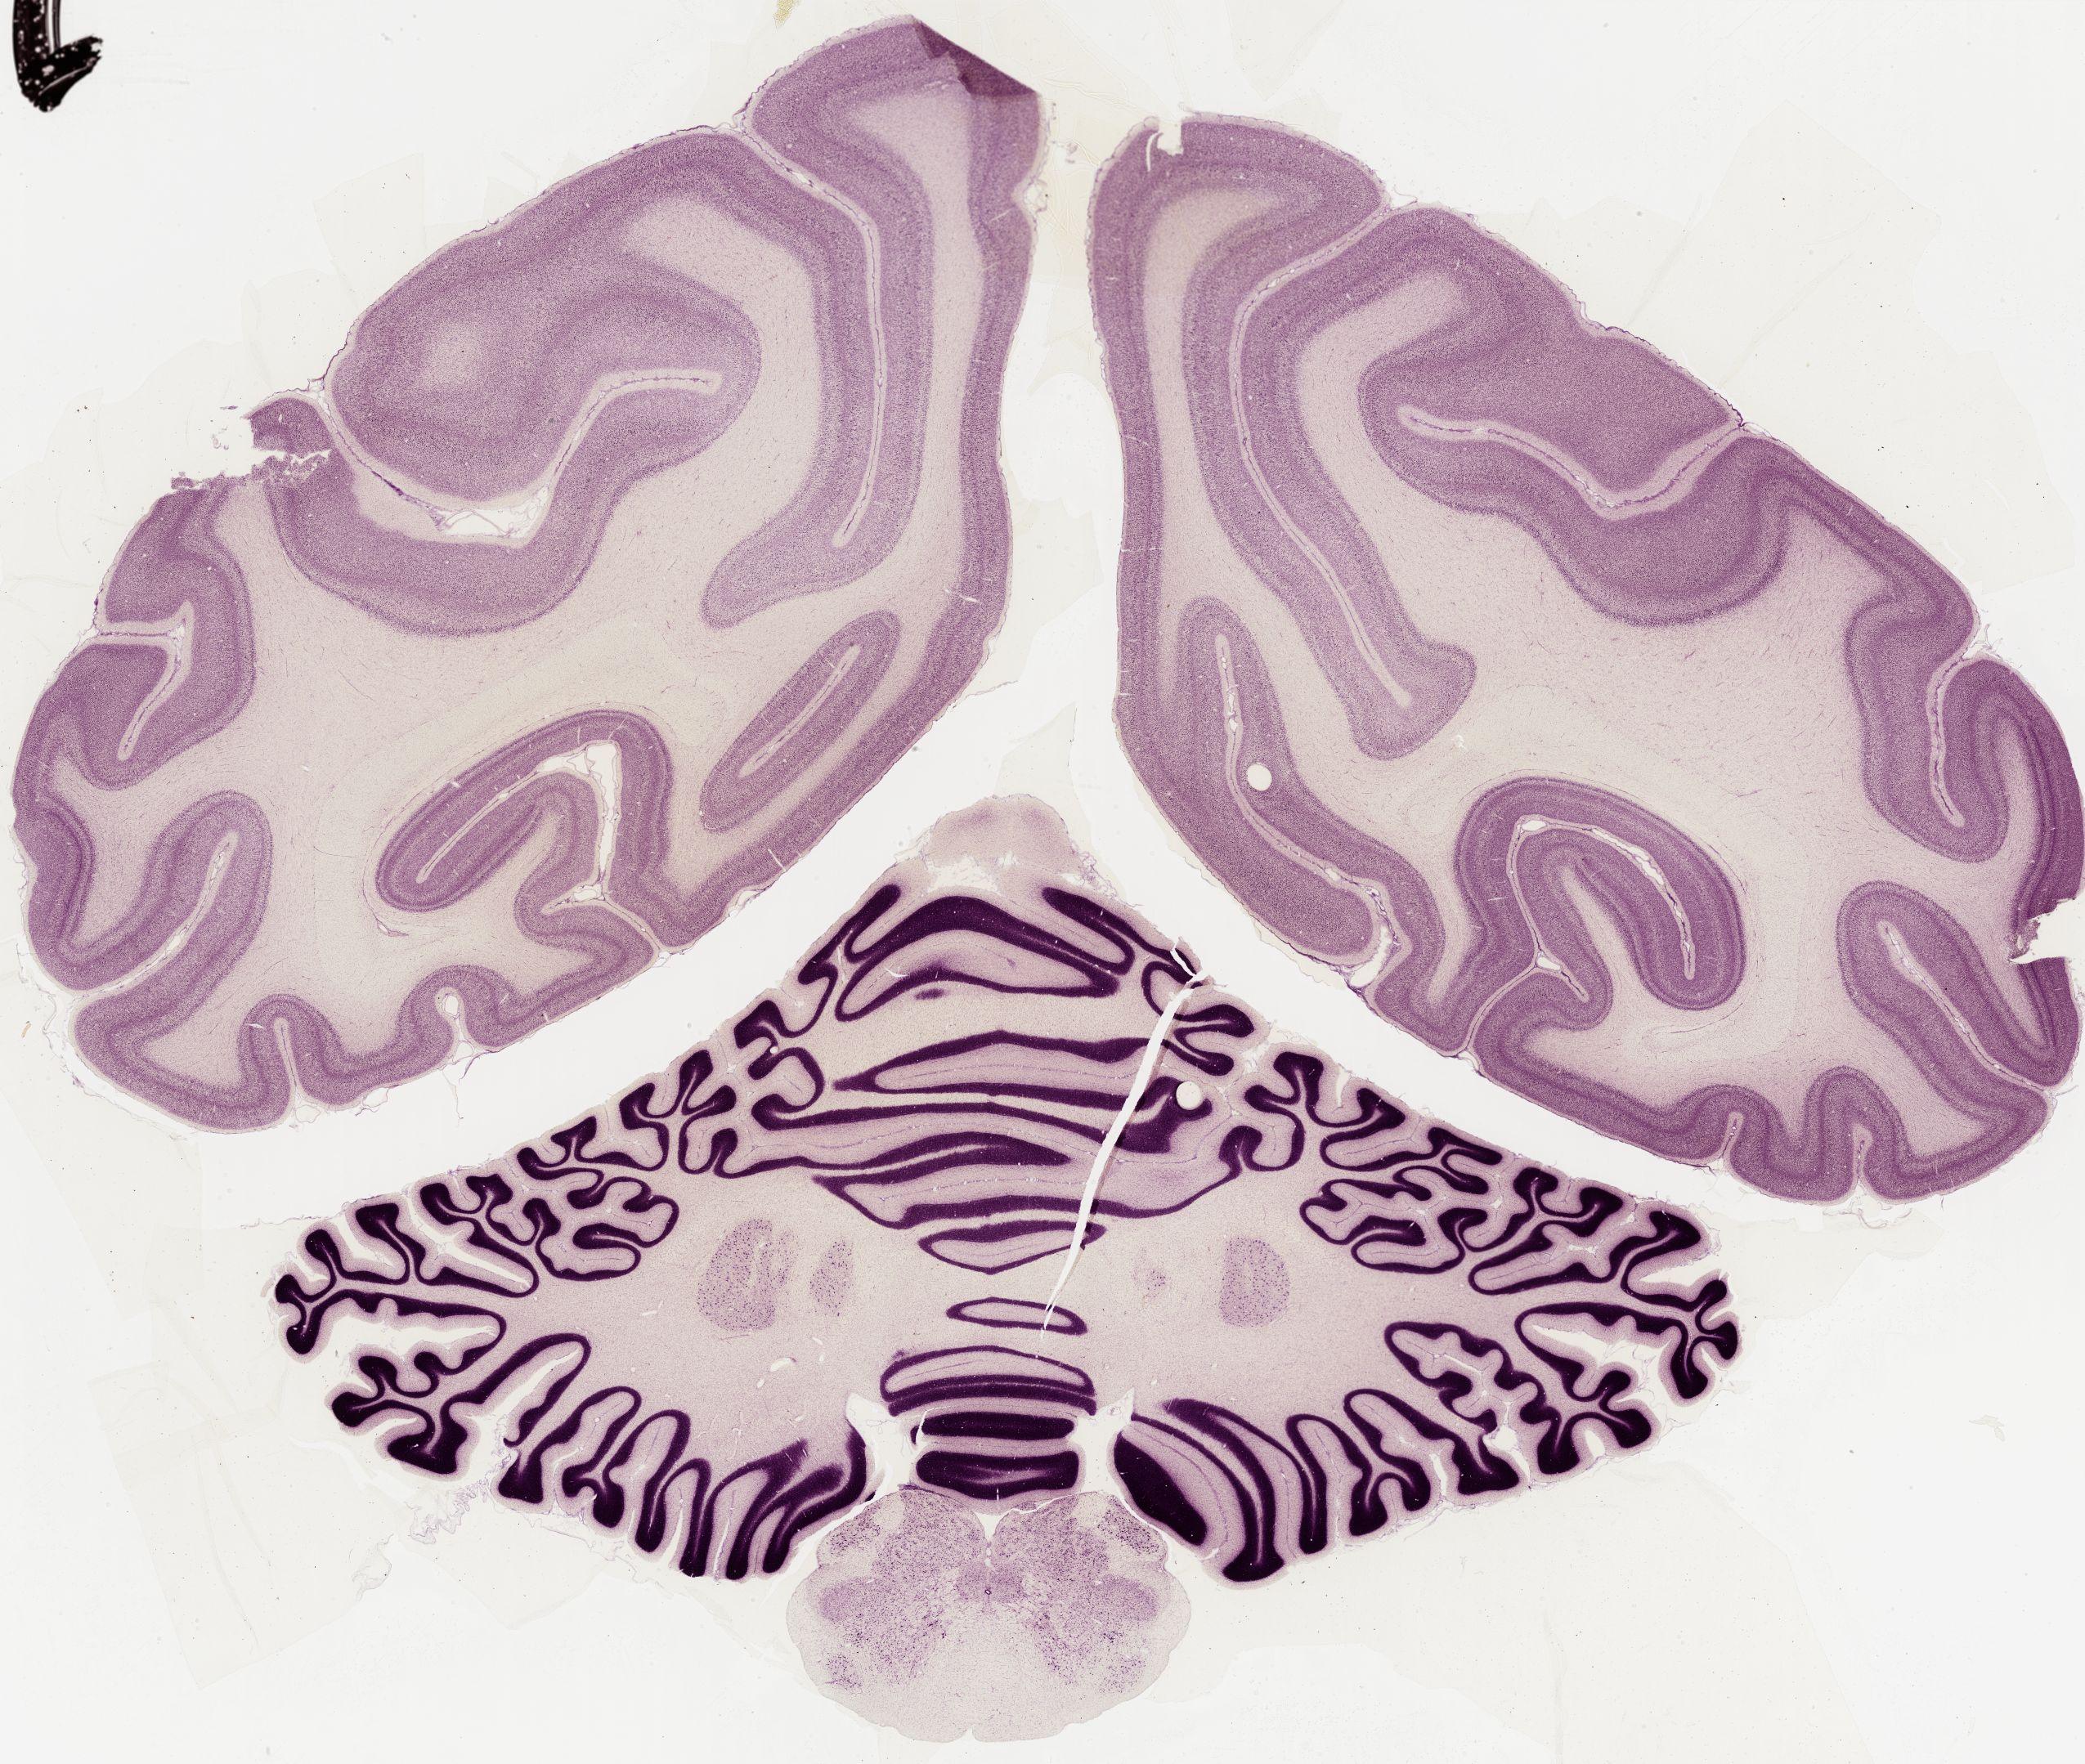

Datasets -> Macaca Mulatta -> Nissl, coronal, histo, Whole-Brain, adult

[ Metadata ]   ·   Source: Edward G. Jones

thumbnail

0582 - labeled